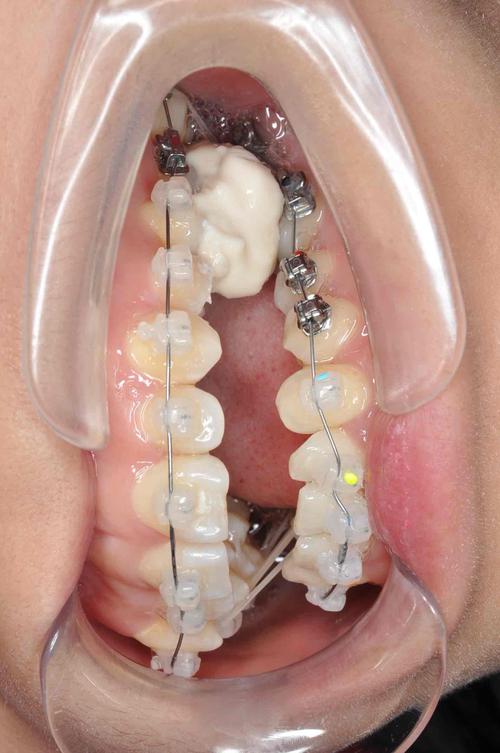

🦷 1. 固定矫治器(最常用)

这是最主流和有效的方法,尤其适用于青少年和成人。

- 原理: 利用粘在牙齿上的托槽(金属、陶瓷或自锁托槽)和弓丝,施加持续、精确的生物力,移动牙齿到理想位置。

- 颌间牵引: 这是建立正常咬合关系的关键步骤,使用橡皮筋(颌间牵引)连接上下颌的牙齿,引导牙齿移动到正确的尖窝交错位置,牵引方向和力量需要精确控制。

- 精细调整: 使用更精细的圆丝或方丝进行精细调整,确保所有牙齿排列整齐,咬合稳定,达到功能性咬合标准。

- 优点: 精确控制牙齿移动三维方向,力量强大,适用范围广,效果稳定可靠。

- 缺点: 口腔异物感较强,口腔卫生维护要求高,治疗周期相对较长(通常1-2年或更长),费用较高。